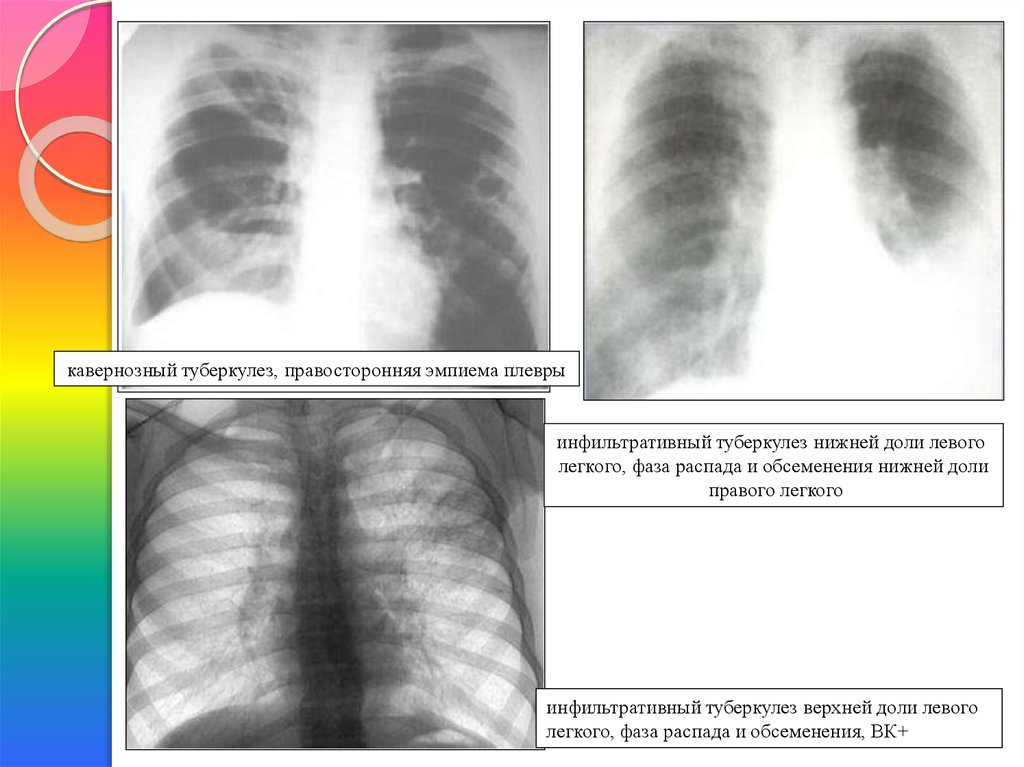

Очаговый и инфильтративный туберкулез презентация - 94 фото